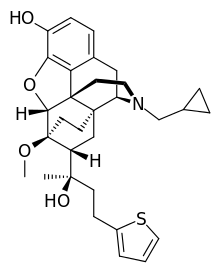

Oripavine derivatives

Thienorphine

- 7-PET

- Acetorphine

- Alletorphine (N-allyl-noretorphine)

- BU-48

- Buprenorphine

- Buprenorphine-3-glucuronide

- Cyprenorphine

- Dihydroetorphine

- Etorphine

- Homprenorphine

- 18,19-Dehydrobuprenorphine (HS-599)

- N-cyclopropylmethylnoretorphine

- Nepenthone

- Norbuprenorphine

- Norbuprenorphine-3-glucuronide

- Thevinone

- Thienorphine

Structures

| Oripavine derivatives | ||||

|---|---|---|---|---|

7-PET 7-PET |

Acetorphine Acetorphine |

Alletorphine Alletorphine |

BU-48 BU-48 |

Buprenorphine Buprenorphine |

Cyprenorphine Cyprenorphine |

Dihydroetorphine Dihydroetorphine |

Etorphine Etorphine |

Homprenorphine Homprenorphine |

18,19-Dehydrobuprenorphine 18,19-Dehydrobuprenorphine |

N-cyclopropylmethylnoretorphine N-cyclopropylmethylnoretorphine |

Nepenthone Nepenthone |

Norbuprenorphine Norbuprenorphine |

Thevinone Thevinone |

Thienorphine Thienorphine |